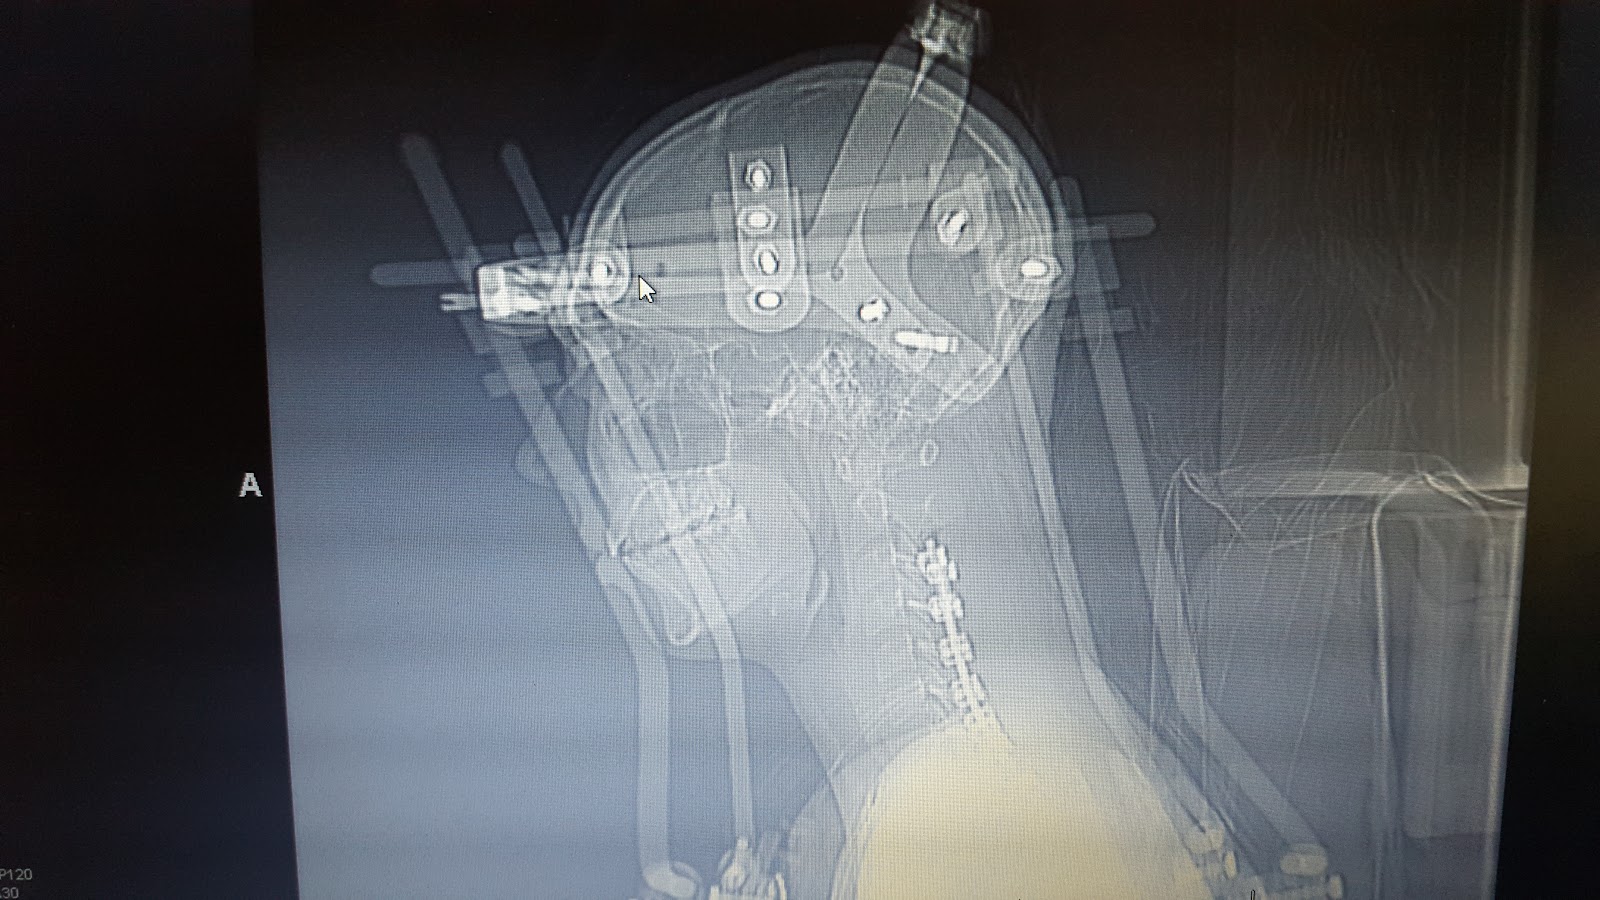

What Does A Neck Halo Look Like . You are fitted with a halo and vest to hold your neck. A halo brace is a metal brace that circles and attaches to your skull. This device is crucial for the management of a. A halo, also known as a halo ring or halo crown, is a piece of equipment that encircles and is fixed to the head of a patient. The ring (or halo) around your head is held in place by four screws (or pins) in your skull. A halo brace holds your neck and bones in a fixed position, like a cast. The ring is attached by four bars to a stiff, lightweight vest. It is used to keep the bones in your cervical spine (neck). A halo brace is a specialized orthopedic device used to immobilize and stabilize the cervical spine (neck) following. The halo brace, also known as the halo vest immobilizer, is a device that restrains the cranium to the torso, offering the most rigid form of external immobilization for the. Review how to care for the halo and yourself, with help from uw health. You have a dislocation or fracture of one or more bones in your neck (vertebrae).

A halo brace holds your neck and bones in a fixed position, like a cast. The ring is attached by four bars to a stiff, lightweight vest. This device is crucial for the management of a. Review how to care for the halo and yourself, with help from uw health. You have a dislocation or fracture of one or more bones in your neck (vertebrae). The halo brace, also known as the halo vest immobilizer, is a device that restrains the cranium to the torso, offering the most rigid form of external immobilization for the. A halo, also known as a halo ring or halo crown, is a piece of equipment that encircles and is fixed to the head of a patient. You are fitted with a halo and vest to hold your neck. It is used to keep the bones in your cervical spine (neck). A halo brace is a specialized orthopedic device used to immobilize and stabilize the cervical spine (neck) following.

What Does A Neck Halo Look Like It is used to keep the bones in your cervical spine (neck). You are fitted with a halo and vest to hold your neck. You have a dislocation or fracture of one or more bones in your neck (vertebrae). The halo brace, also known as the halo vest immobilizer, is a device that restrains the cranium to the torso, offering the most rigid form of external immobilization for the. It is used to keep the bones in your cervical spine (neck). A halo brace is a metal brace that circles and attaches to your skull. A halo, also known as a halo ring or halo crown, is a piece of equipment that encircles and is fixed to the head of a patient. A halo brace is a specialized orthopedic device used to immobilize and stabilize the cervical spine (neck) following. The ring (or halo) around your head is held in place by four screws (or pins) in your skull. The ring is attached by four bars to a stiff, lightweight vest. Review how to care for the halo and yourself, with help from uw health. This device is crucial for the management of a. A halo brace holds your neck and bones in a fixed position, like a cast.